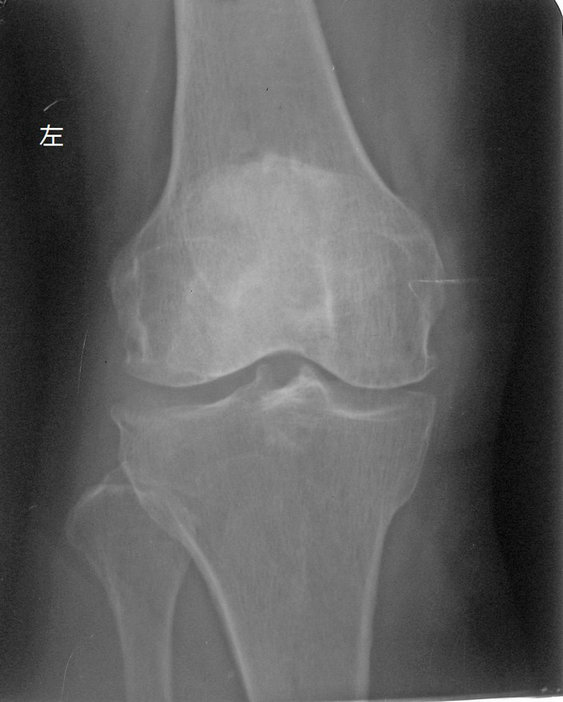

以下是引用拾荒者在2010-7-5 21:08:00的发言:[br]1.膝关节退行性变;2.颈椎未见明显异常。

以下是引用hexue在2010-7-5 22:47:00的发言:[br]1.膝关节退行性变;2.颈椎未见明显异常。 [br] [br]

以下是引用随光逐影在2010-7-6 7:11:00的发言:[br]病例1:双膝关节退行性骨关节病。[br]病例2:1)颈椎未见明确异常。2)一侧下颌智齿横位阻生。